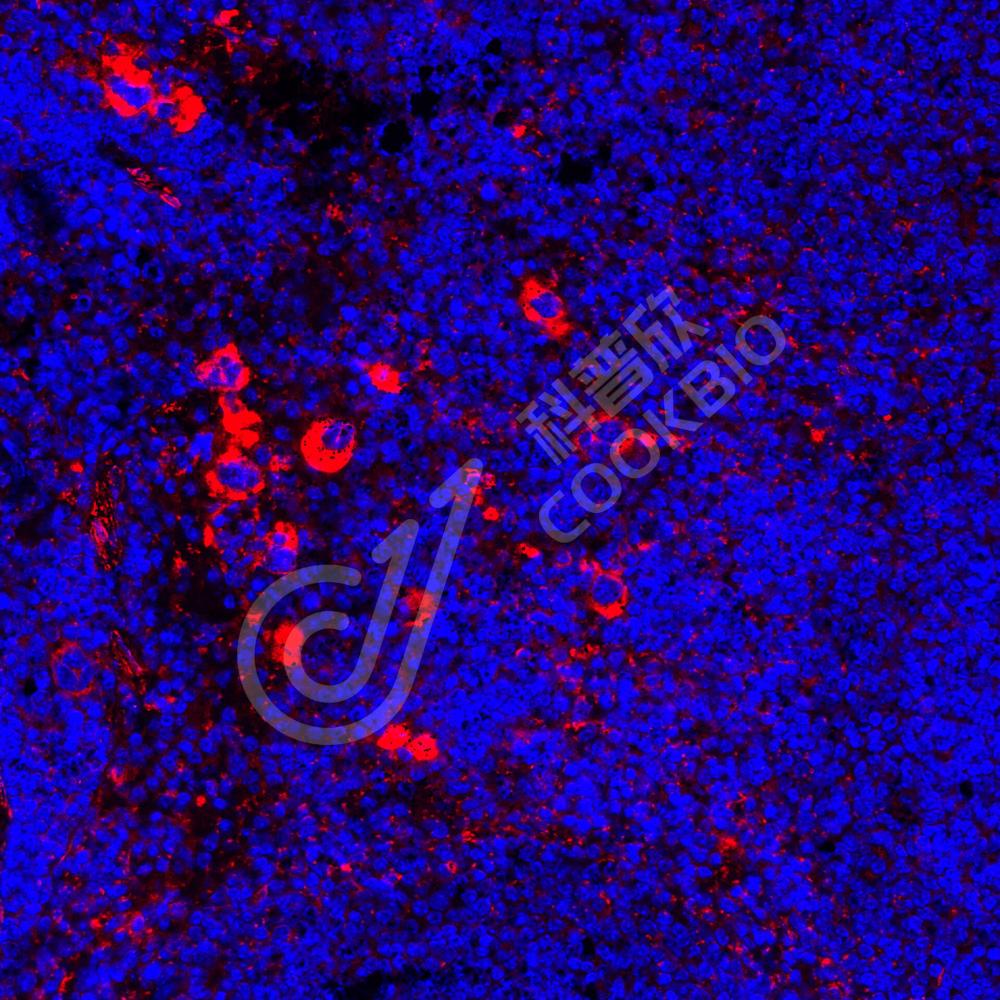

IF检测LITAF蛋白(货号 K1338970)(红色).

样品: 小鼠脾, 4%多聚甲醛 (货号KSG1101) 固定12-24小时.

抗原修复: Tris-EDTA抗原修复液(pH 9.0) (KSG1203), 98℃, 20分钟.

封闭: 3% BSA(货号KSGC305010)的PBS溶液, 室温孵育30分钟.

—抗: 1: 7200稀释, 4℃ 孵育过夜.

二抗: Cy3标记山羊抗兔IgG (H+L) (货号KB63909), 1: 300稀释, 室温孵育1小时.